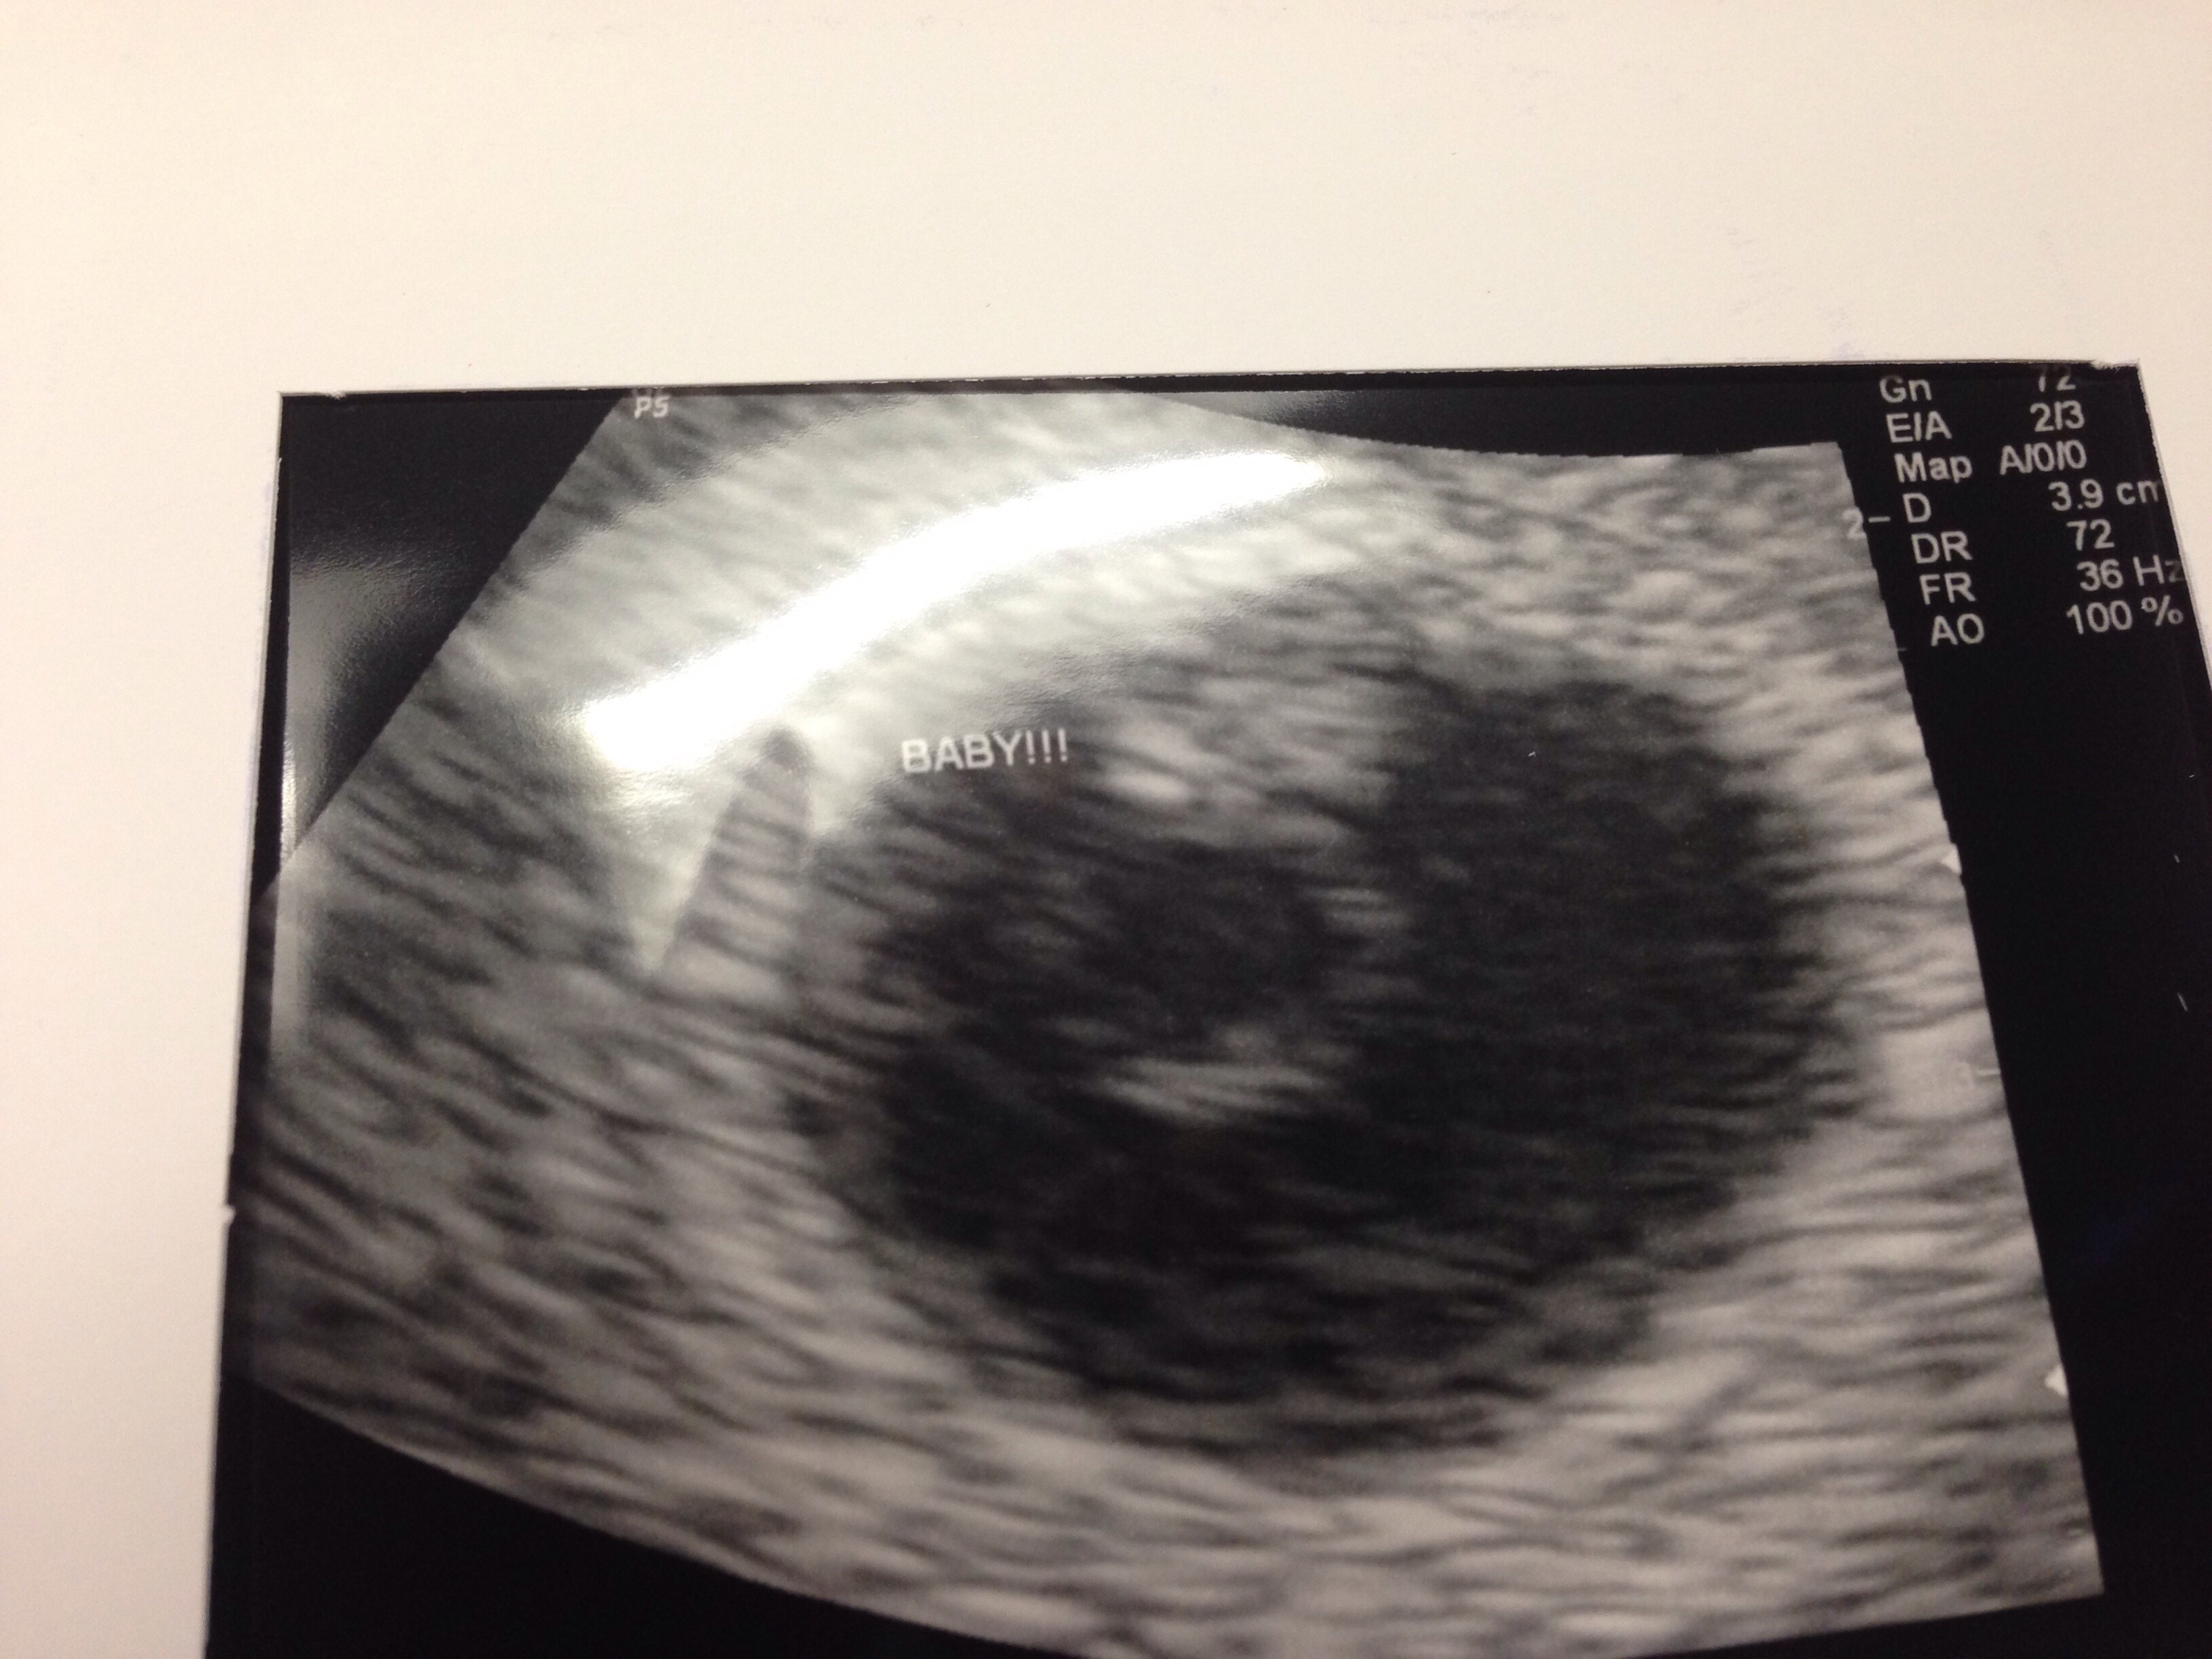

Just got this yesterday our first ultrasound of our babe! The little black dot in the white space on the left. I was on 5w3d. I go back next Tuesday so I'll be 6w4d and hopefully we'll get to see/hear the heartbeat then!